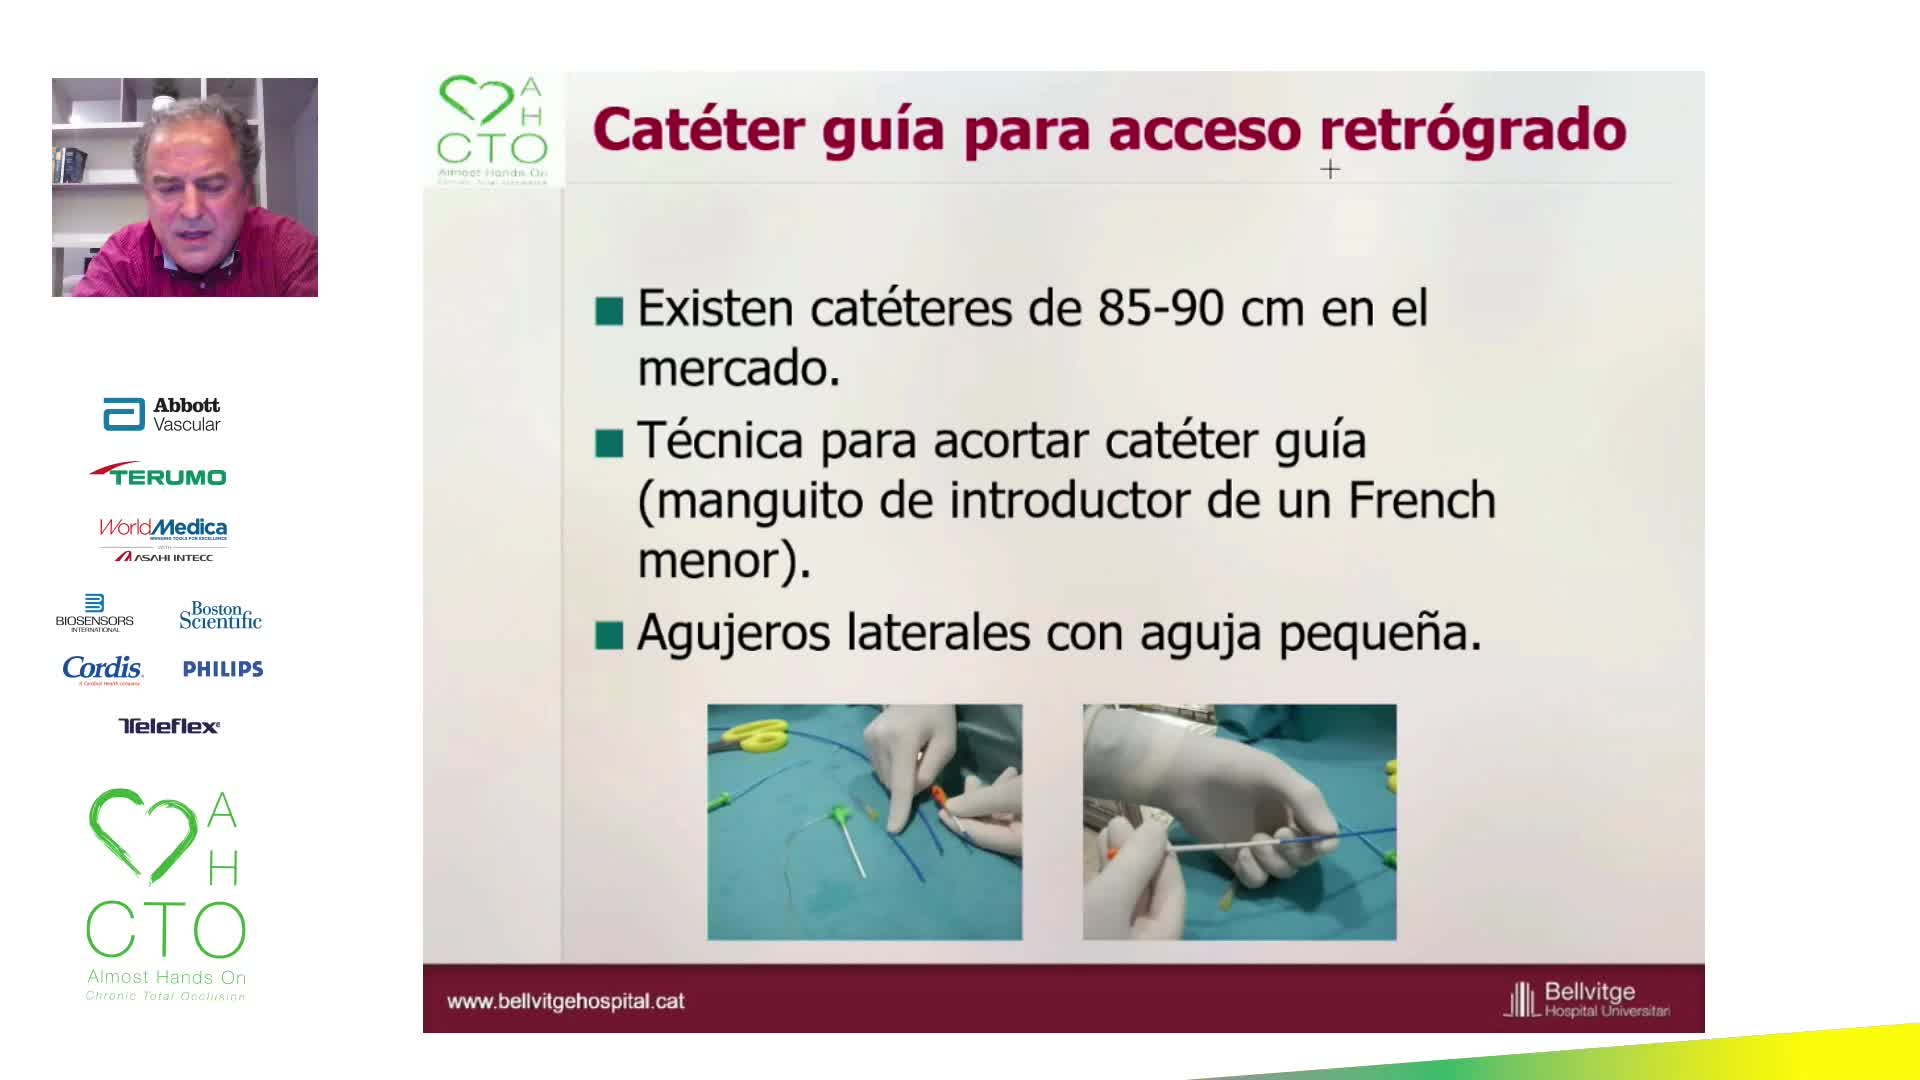

12th AHO meeting December 2020